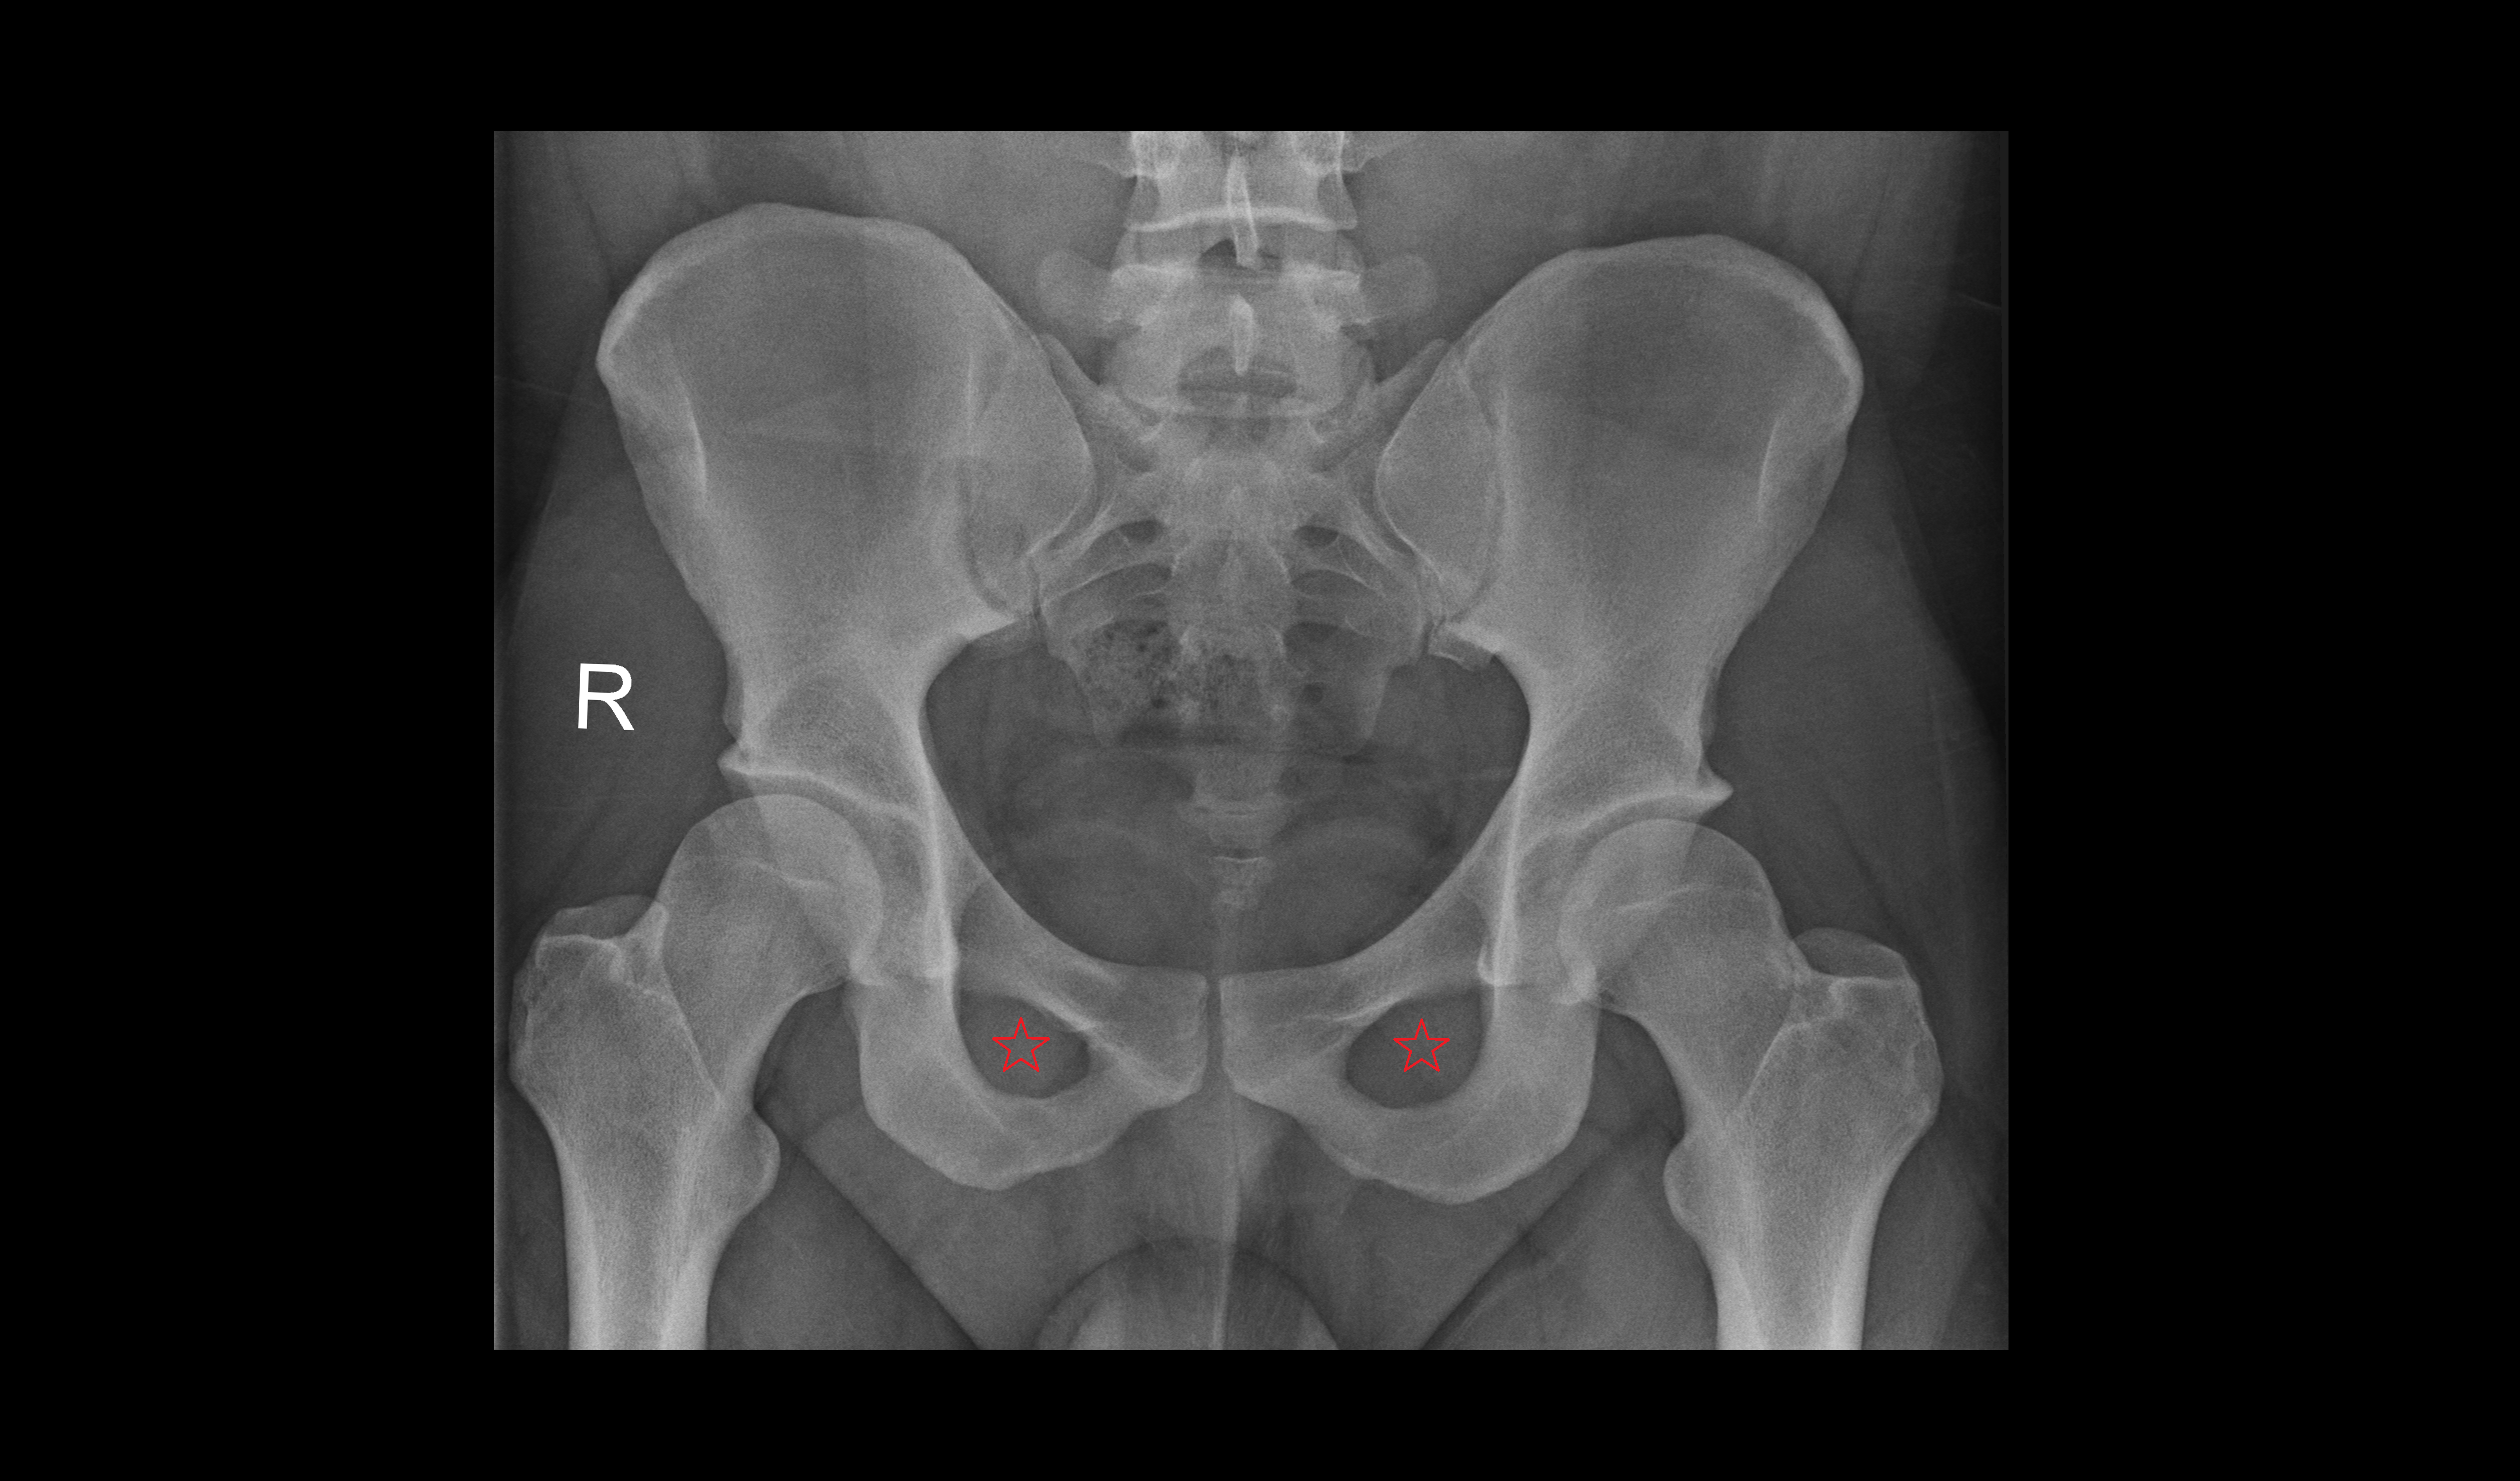

- Acetabular margin (Acetabular rim)

- Acetabulum

- Head of femur

- Neck of femur

- Acetabular labrum

- Hip joint